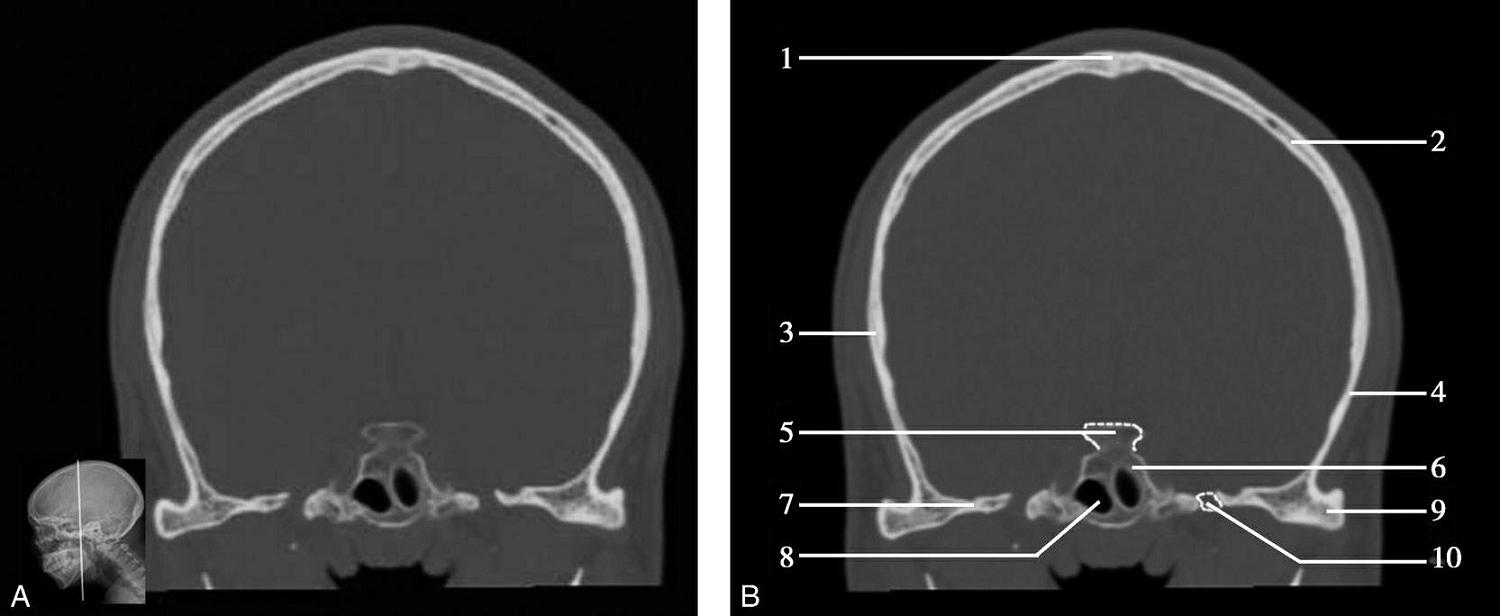

重要结构:卵圆孔、棘孔、破裂孔、斜坡、颞骨岩部、颈静脉孔(图1-2-1、图1-2-2)。

图1-2-1 颅底层面

A.横断面;B.横断面标注

1.晶状体;2.筛窦;3.颞肌;4.中颅窝底;5.外耳道;6.延髓;7.乙状窦;8.小脑半球;9.眼球;10.眼眶;11.上颌窦;12.蝶窦;13.乳突;14.耳郭;15.小脑蚓部;16.枕内隆凸

图1-2-2 颅底层面(骨窗)

1.鼻骨;2.筛窦纸板;3.颧骨眶突;4.翼腭窝;5.蝶骨大翼;6.卵圆孔;7.破裂孔;8.颞骨颧突;9.棘孔;10.斜坡;11.颞骨岩部;12.乳突;13.颈静脉孔;14.枕乳突缝;15.枕骨;16.枕内隆凸

层面前部呈开口向前的“V”字形,正中为鼻中隔,向两侧依次为筛窦和眼眶,眼眶内前部为眼球,后部为眶脂体。翼腭窝位于眼眶后部,窝内含有脂肪并有上颌神经通过。层面中部为蝶骨体,蝶骨体中部可见含气蝶窦,蝶窦后方为枕骨基底部,两者呈前后关系,其上面构成斜坡。蝶窦两侧为蝶骨大翼,其后外侧缘处由前向后可见卵圆孔和棘孔,分别有下颌神经和脑膜中动脉通过。斜坡外侧、岩骨尖前方为破裂孔。蝶骨大翼与眶外侧壁的颧骨借颧弓相连,颧弓和蝶骨大翼之间有咬肌及颞肌。层面中部外侧为外耳道。颞骨岩部呈“八”字形,相互之间借破裂孔软骨、蝶岩软骨结合和岩枕软骨结合连接。岩部后外侧的乳突部内可见乳突小房,乳突部与枕骨相接。岩骨后部可见颈静脉孔,内有颈内静脉、舌咽神经、迷走神经和副神经通过。层面后部为颅后窝,其内可见延髓,延髓前方为延髓前池,内有椎动脉,后外侧为小脑半球下部,后方为第四脑室、小脑扁桃体及小脑蚓部。